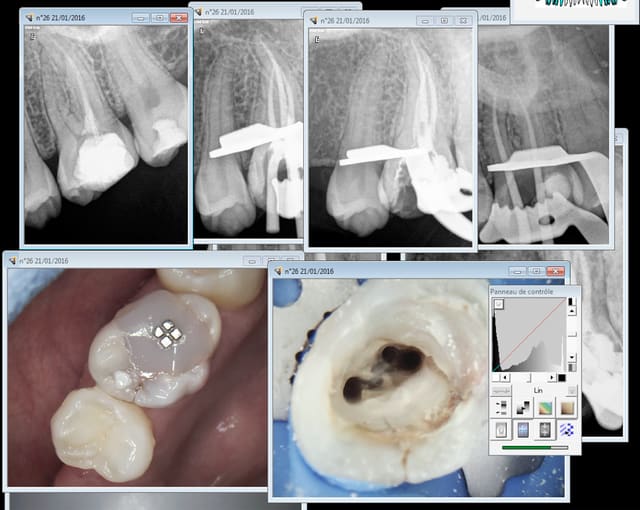

Tiens mon cher Bjorn , amuse toi , elle date de ce matin tout frais moulu . Mince, prends une loupe, ça dépasse ? manque un canal ? pas la digue ? rhaaaa je vais en enfer ou j'ai encore le droit de poster ?

Chicot faut m'excuser j'ai pas les photos !

Il y en a qui en mettent trop de la gutta et d'autres pas. Ca fait une moyenne. -))

tiens ? mais je vois qu'on fait aussi des inlay core ! -)

Capture d e cran 2016 01 21 17.43 - Eugenol

"tiens ? mais je vois qu'on fait aussi des inlay core ! -)"

ha ben non , ça c'est pas moi ! mais j'en mets aussi mais c'est pas systématique hein !